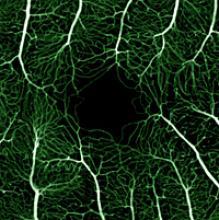

The retina viewed by phase variance-OCT.

Phase-variance OCT (top) can reveal blood vessels over the retina (yellow and red) and underneath it in a layer of tissue called the choriocapillaris (green). In this person with AMD, it also reveals areas of choriocapillaris loss (blue arrowheads). This level of detail isn’t seen by standard fluorescein angiography (bottom). Republished from Kim et al., PNAS.

In an NEI-funded study, Werner and colleagues used phase-variance OCT to examine the eyes of two volunteers in their 60s. One had no history of eye disease and the other had a type of advanced AMD called geographic atrophy. The researchers were able to see retinal vessels, as well as small vessels in a layer of tissue underneath the retina called the choriocapillaris.

In the person with AMD, they detected a loss of these small choroidal vessels, which typically aren’t visible with fluorescein angiography or other standard methods.